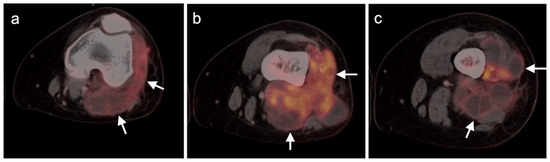

- Lisle, J.W.; Eary, J.F.; O’Sullivan, J.; Conrad, E.U. Risk Assessment Based on FDG-PET Imaging in Patients with Synovial Sarcoma. Clin. Orthop. Relat. Res. 2008, 467, 1605–1611. [Google Scholar] [CrossRef] [PubMed] [Green Version]

- Chang, K.J.; Lim, I.; Park, J.Y.; Jo, A.R.; Kong, C.B.; Song, W.S.; Jo, W.H.; Lee, S.Y.; Koh, J.S.; Kim, B.I.; et al. The Role of 18F-FDG PET/CT as a Prognostic Factor in Patients with Synovial Sarcoma. Nucl. Med. Mol. Imaging 2014, 49, 33–41. [Google Scholar] [CrossRef] [PubMed] [Green Version]